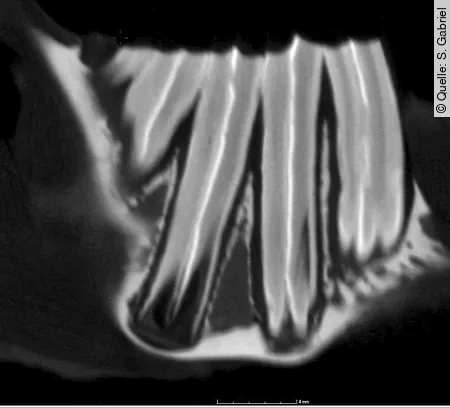

Eine überlagerungsfreie Darstellung aller Backenzähne ist am Schädel des Kleinsäugers nicht möglich. Daher müssen hochauflösende Röntgenbilder (Abb. [2]) bei standardisierter Lagerung in mehreren Ebenen angefertigt werden, um Zähne und Kiefer sicher beurteilen zu können. Die in diesem Artikel dargestellten CT-Bilder wurden experimentell mit einem Mikro-CT aus der Werkstoffprüfung an Knochenpräparaten angefertigt (Abb. [3]). Sie sind in ihrer Auflösung nicht mit den üblicherweise vorhandenen klinischen CT-Bildern vergleichbar. Gerade für die feinen und feinsten Veränderungen an Zähnen und Kiefern ist die klassische (Dental-)Röntgentechnik immer noch unübertroffen [[5]]. Zur isolierten Darstellung der Unterkieferäste wird eine Schrägprojektion mit einer Kippung von etwa 40° verwendet.

Häufig wird angefragt, ob man einen „störenden“ Backenzahn, z. B. wegen sublingualer Spitzenbildung, nicht einfach ziehen kann. Dazu ist zu bemerken, dass sich ein wurzelgesunder Molar nicht aus der Zahnreihe entfernen lässt, ohne die Nachbarzähne zu schädigen. Das gelingt höchstens bei den endständigen Molaren. Abb. [5] zeigt die bilophodonte Innenstruktur der Molaren. Dies bedeutet, dass ein zusammengesetzter elodonter Zahn aus 2 nebeneinander angeordneten und verbundenen Zahnkörpern besteht, von denen jeder ein eigenes Pulpenorgan besitzt.